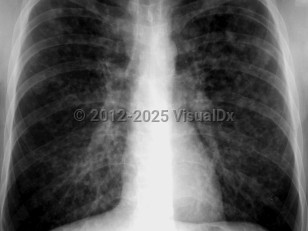

Varicella pneumonia in Child

Chest radiograph changes that can be seen include interstitial changes and nodular infiltrates.